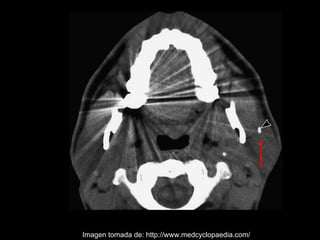

La sialolitiasis es la formación de obstrucciones mineralizadas en las glándulas salivales, causadas por el depósito de calcio y fósforo. Puede presentarse en las glándulas salivales mayores y menores, causando inflamación e hinchazón e incluso dolor durante las comidas. Los sialolitos se ven en radiografías como densidades radiopacas de varias formas y tamaños dentro de los conductos glandulares. El diagnóstico diferencial incluye otras imágenes radiopacas en los tejidos blandos.